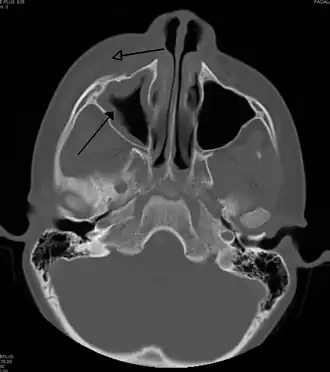

Maxillary sinusitis caused by a dental infection associated with periorbital cellulitis -

Frontal sinusitis -